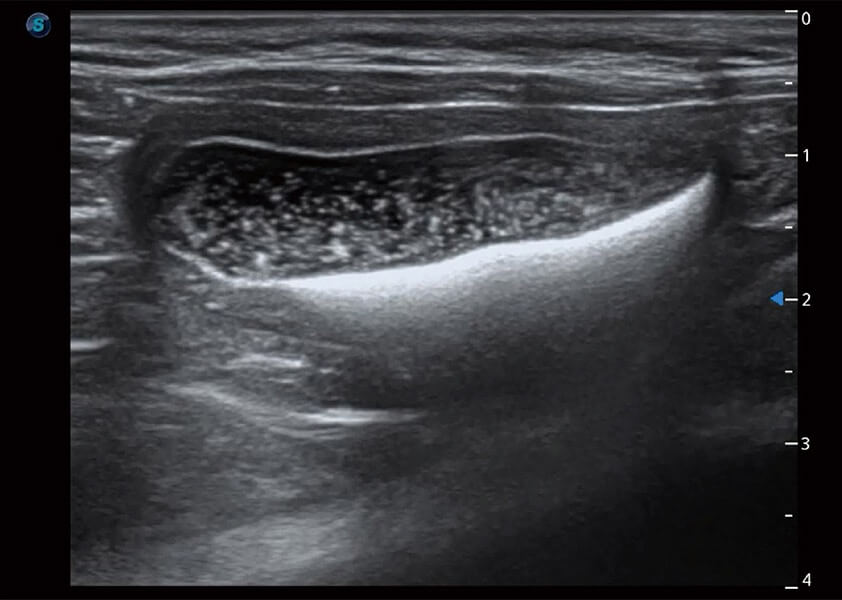

ProPet 60 作为一款高端台式动物超声设备,为动物医生的日常诊断提供了一系列贴合动物临床需求、解决临床实际问题的高级成像功能。凭借全系列高清探头,满足医生对腹部、心脏、生殖、浅表、肌骨等成像的所有需求,切实帮助您提升检查效率,提高诊断信心。

动物是人类最亲密的朋友和最值得信赖的伙伴。milan米兰也一直致力于探索动物专用的超声影像解决方案。 全新推出的ProPet系列,是milan米兰在动物超声影像智能化、专业化、精准化的一次跨越式革新。动物不能用言语来表述自己的不适,通过超声影像,ProPet系列搭建了动物医生与不同物种沟通的“桥梁”,为动物医生注入了“治愈之力”。